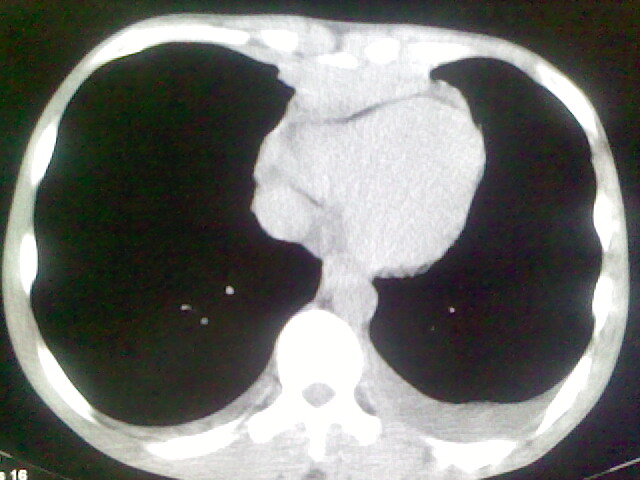

以下是引用杀毒软件在2008-9-3 6:11:00的发言:[br]侵袭性胸腺瘤------一般不侵到气管旁[br][br]考虑----纵隔淋巴瘤,心包及胸膜受累

以下是引用wzr在2008-9-3 5:30:00的发言:[br]侵袭性胸腺瘤

以下是引用随光逐影在2008-9-3 7:07:00的发言:[br]1)考虑淋巴瘤可能。2)双侧胸腔积液(以左侧为甚)。3)心包积液。